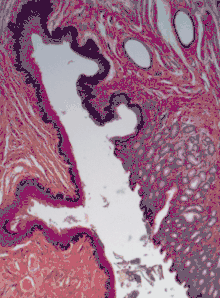

Мочеотводящие органы (почечные лоханки, мочеточники, мочевой пузырь, уретра) выстланы особым переходным эпителием, который даёт возможность этим органам сильно растягиваться при заполнении мочой. Своё название он получил в связи с тем, что ранее считалось, что он является переходной формой между многослойным столбчатым и многослойным плоским эпителиями. Поскольку переходный эпителий встречается только в мочеотводящих путях, его также называют уротелием[42]. Переходный эпителий обычно достигает 4—6 клеток в толщину[43]. В переходном эпителии выделяют три слоя: базальный, промежуточный, поверхностный. Базальный слой образуют невысокие цилиндрические или кубические клетки[32]. Промежуточный слой образован клетками многоугольной формы. Клетки поверхностного слоя очень крупные, нередко содержат два или три ядра, и в зависимости от степени растяжения стенки органа и его заполненности мочой имеют куполообразную или уплощённую форму. Когда стенка органа сокращается, некоторые клетки промежуточного слоя выходят на границу с поверхностным слоем и принимают грушевидную форму, а расположенные над ними поверхностные клетки становятся куполообразными. Когда орган заполнен мочой, но его стенка не сокращается, эпителий становится более тонким, поверхностные клетки принимают уплощённую форму[44].